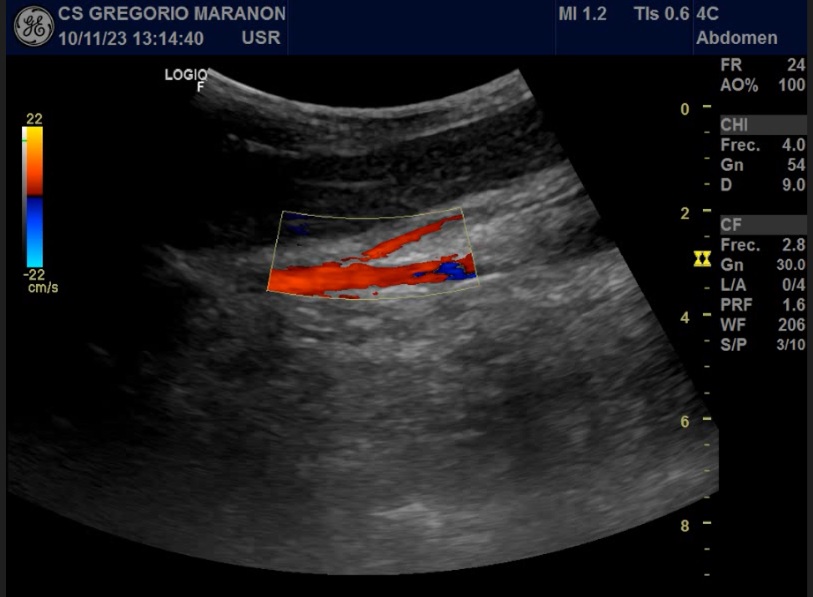

Ecografía clínica donde en el plano transversal vemos una distancia entre Arteria mesentérica superior (AMS) y Aorta de 3 mm y un ángulo entre ellas de 14,3º.

Fisiológicamente, el ángulo formado entre la AMS y la Aorta oscila entre 38 y 65º con una distancia entre ambas de 10 a 28 mm. Cuando estas medidas son menores de 25º o de 8 mm respectivamente, se produce una compresión de la tercera porción del duodeno.

El diagnóstico de esta entidad suele retrasarse debido a su inicio insidioso. La ecografía es un método muy sensible para el diagnóstico del SAMS con una alta correlación con la tomografía axial.